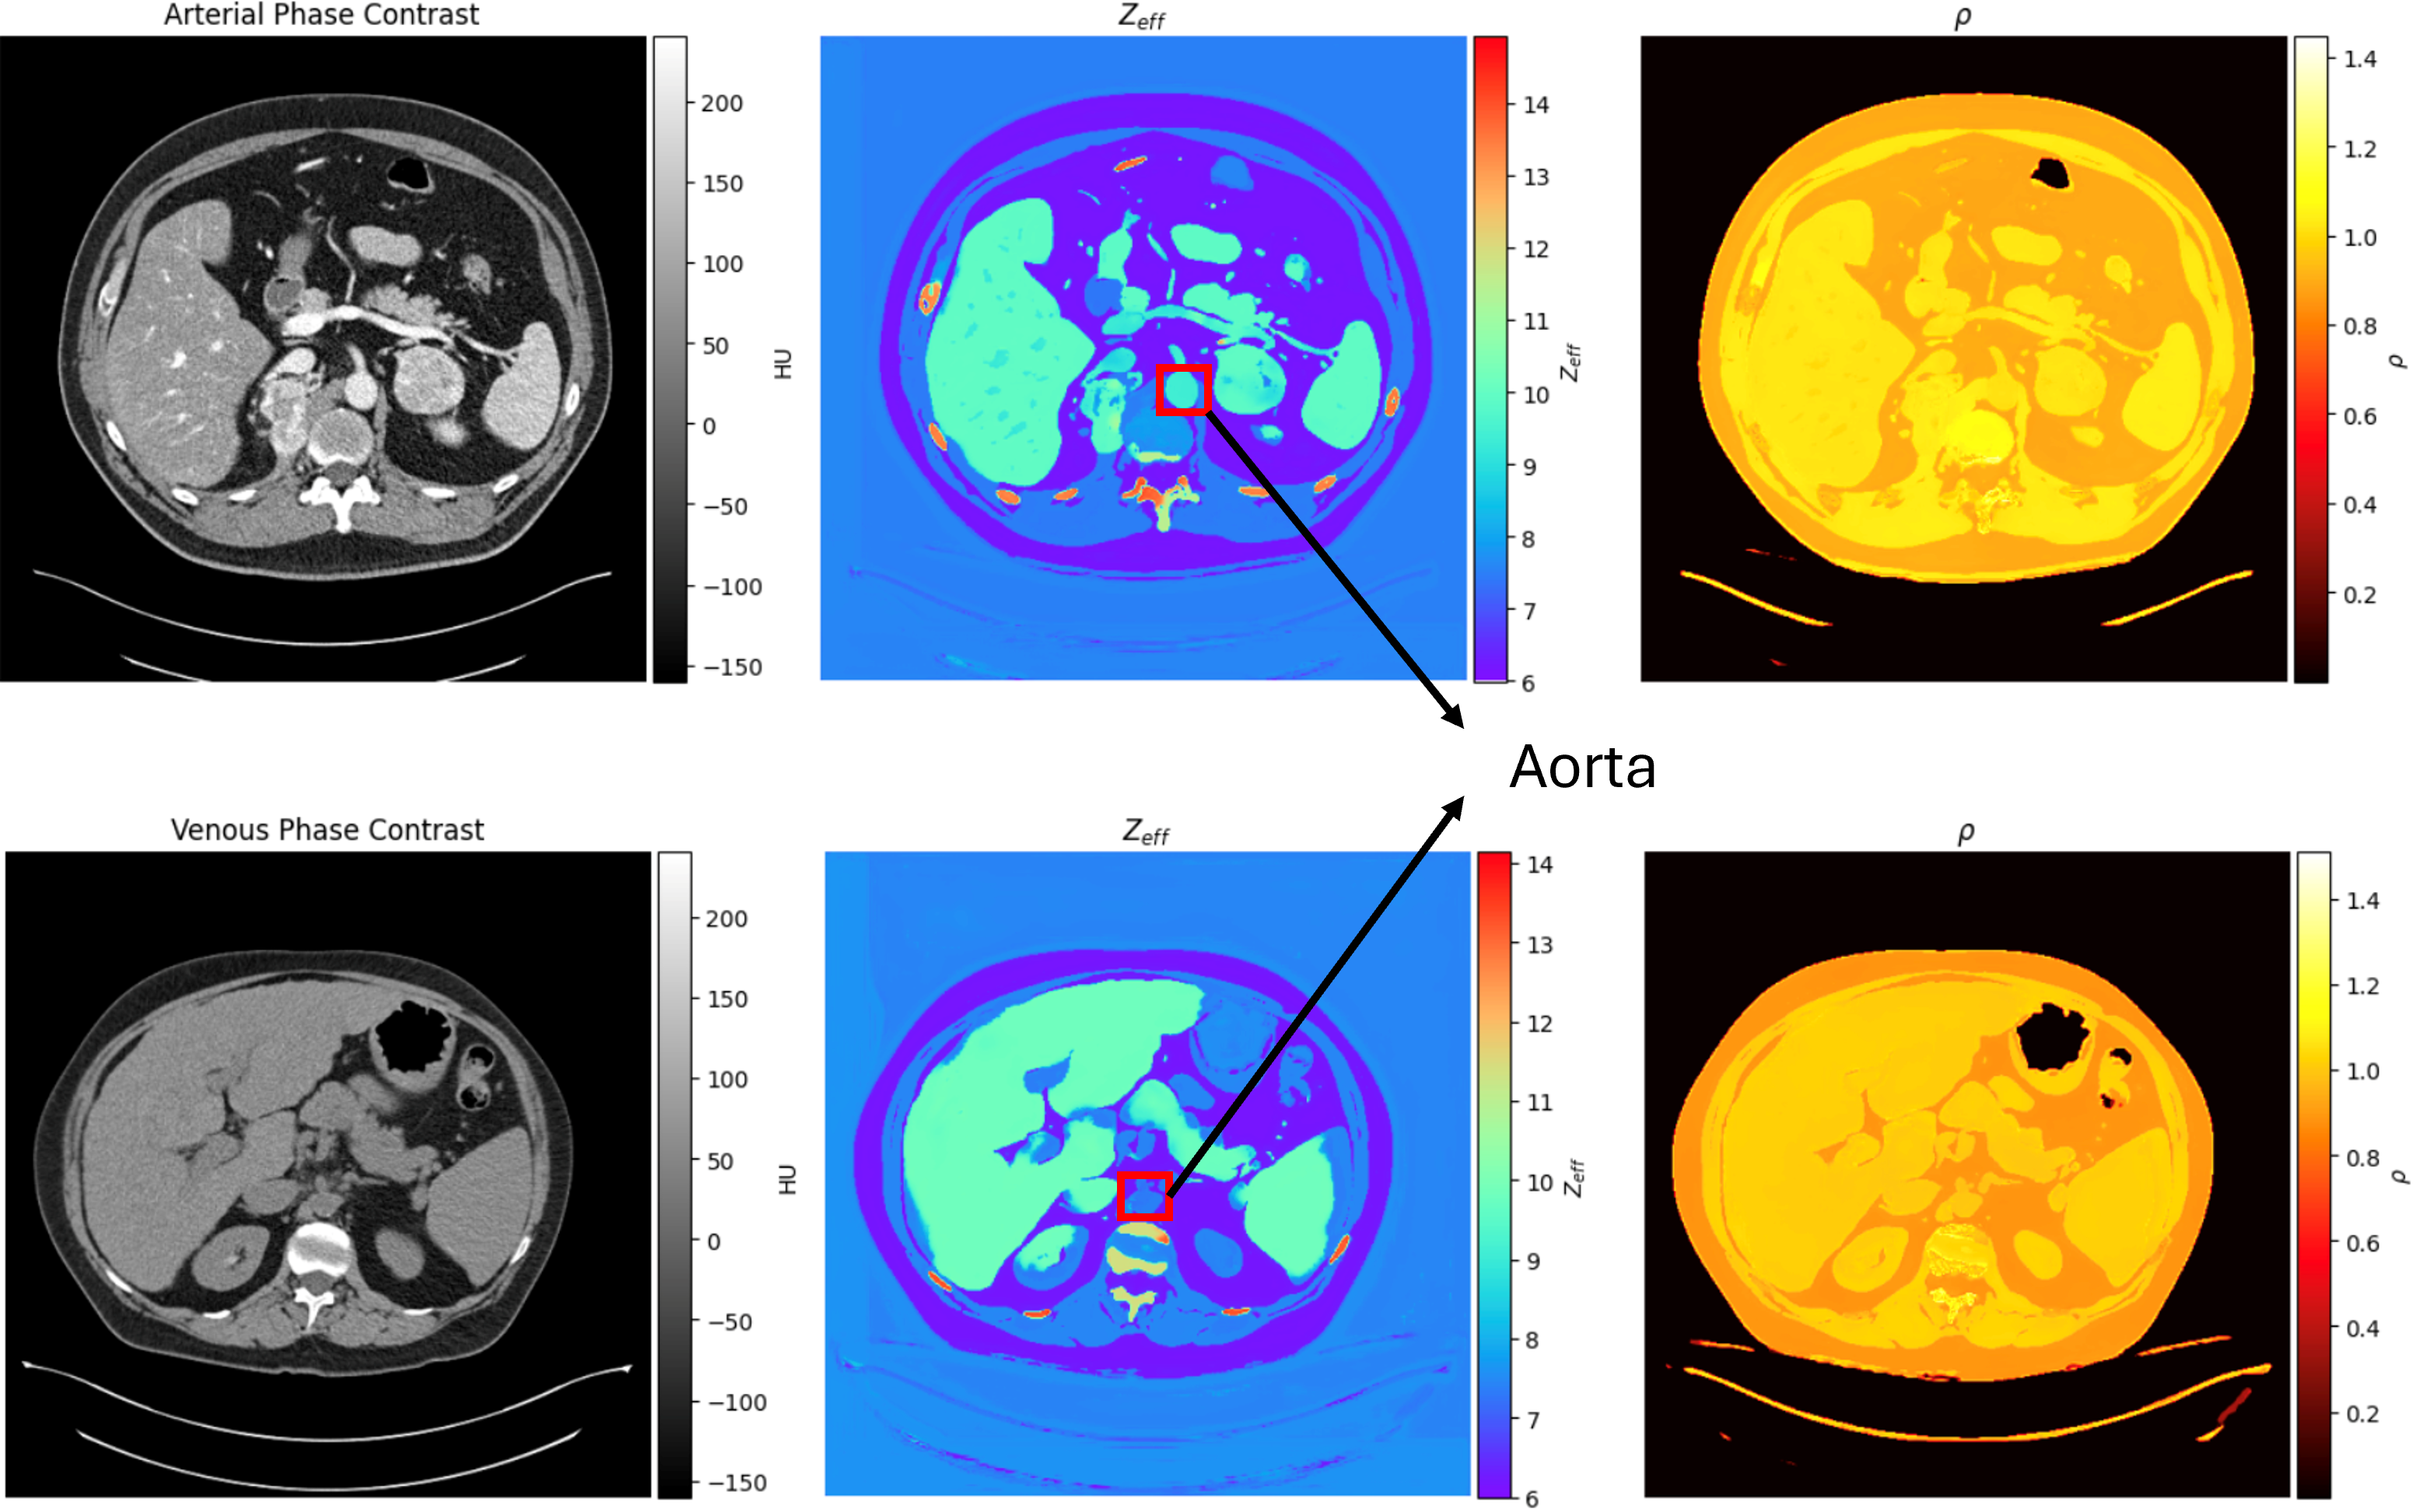

• Material Decomposition: Extended this work to spectral CT, using Deep Learning to accurately decompose images into their constituent materials (iodine, water, bone) for advanced diagnostics.

• J.H. Valand, Mojtaba Zarei, ... et al., "Truth-Based Physics Informed Estimation of Material Composition in Spectral CT," AAPM, 2024.

Figure: Clinical material decomposition images from spectral CT generated using a physics-informed GAN trained exclusively on digital twin data.